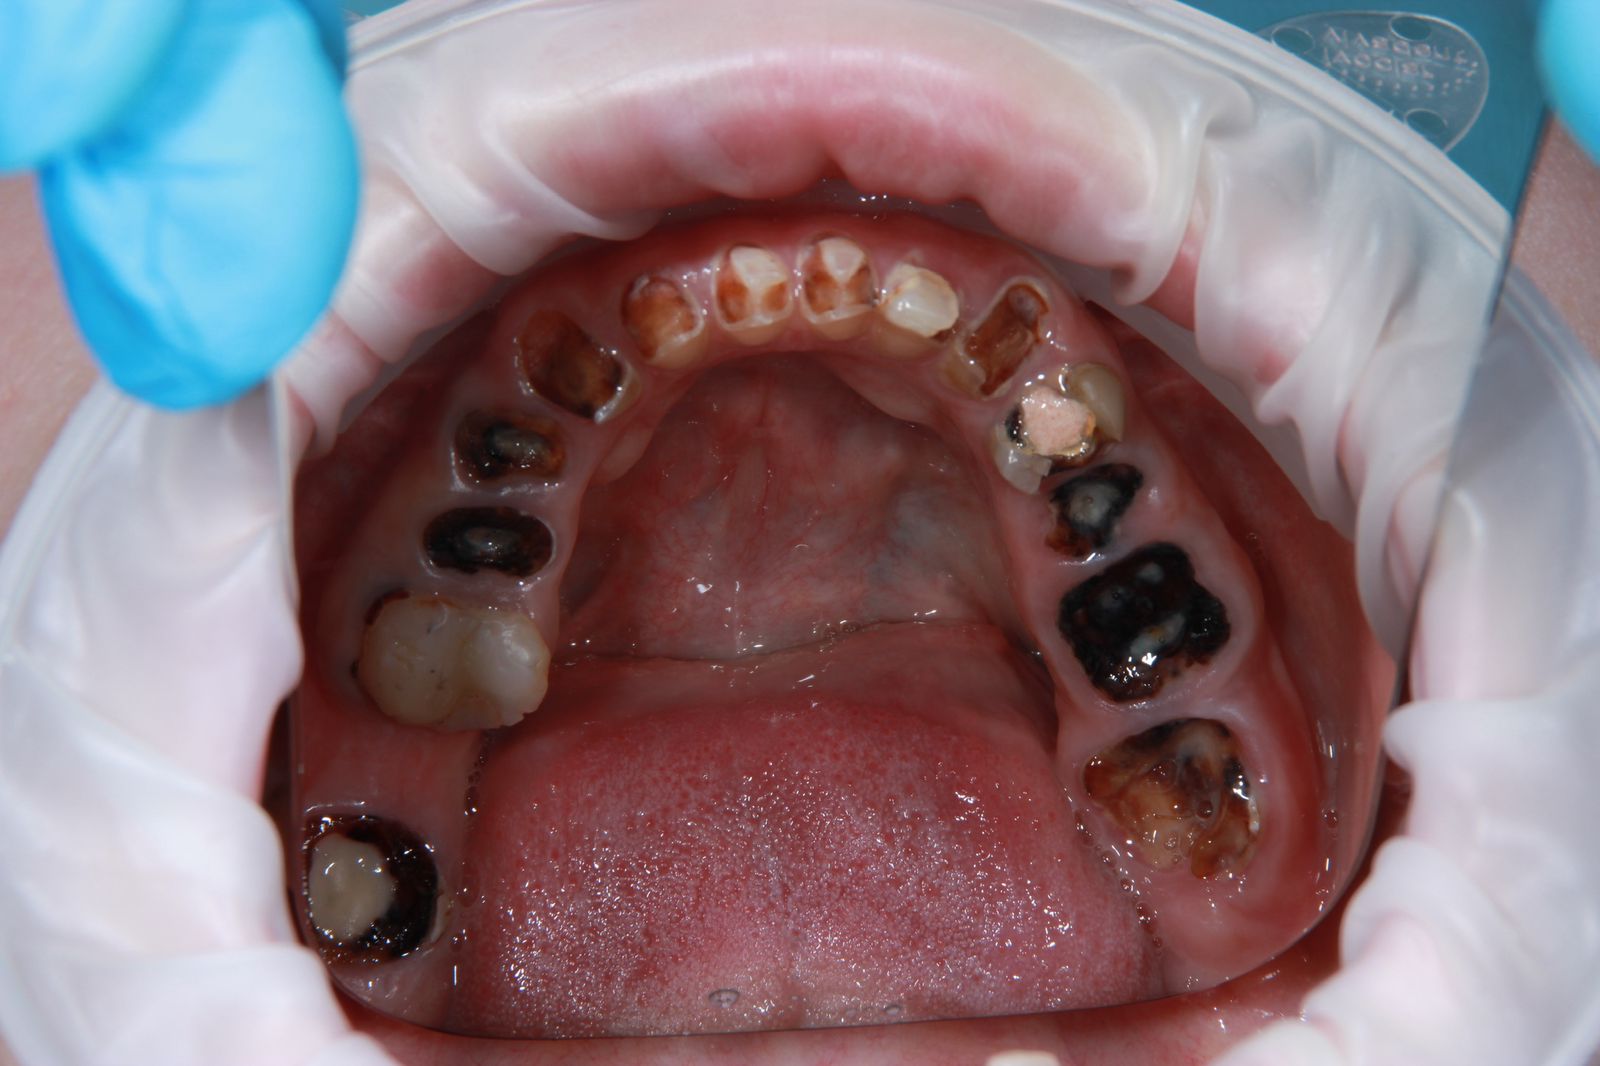

Очень часто у употребляющих снижено понятие боли, поэтому зубы могут быть в очень плохом состоянии. То есть они могут либо отсутствовать, от них остаются чёрные корешки, могут быть обломаны, стерты. Часто шейки могут быть от темно-коричневого до черного цвета, крошится просто на глазах. Покрыты огромным количеством зубного налета, камнями. При этом ни один из симптомов может не доставлять боли, а лишь эстетический дискомфорт.